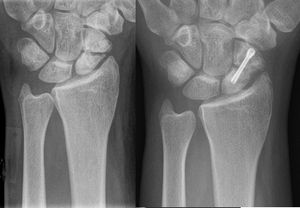

일반적으로 골절된 뼈의 병력이 확실하다. 불유합이 있는 환자는 골절 부위의 지속적인 통증을 호소하며 골절 부위에서 비정상적인 움직임이나 딸깍거리는 소리를 느낄 수 있다. 골절된 뼈의 X-선판은 골절 부위에서 방사선 투과선이 확인된다. 불유합의 경우 골절선이 계속 보이거나 골절 끝 부위에 경화가 확인된다. 또한 뼈가 낫는 데 형성되는 작은 뼈 조직인 가골 형성이 없거나, 가골이 형성되었어도 골절 사이를 연결하지는 않는다.[1]

X-ray 판독에 의문이 있을 경우, 스트레스 X-ray, 단층 촬영 또는 CT 스캔을 사용하여 확인할 수 있다.[1]

불유합의 진단은 임상의가 추가적인 중재 없이는 뼈가 더 이상 치유되지 않을 것이라고 판단할 때 내려진다. 미국 식품의약국(FDA)은 불유합을 최소 9개월 이상 되었고, 지난 3개월 동안 방사선학적 치유 징후를 보이지 않은 골절로 정의한다.[9] 컴퓨터 단층 촬영(CT)은 골절 부위를 더 자세히 보여주며, 골절 부위의 치유 정도를 평가하는 데에도 사용될 수 있다. 혈액 검사를 통해 환자의 칼슘과 비타민 D와 같은 영양소 수치가 적절한지 평가할 수 있다. 또한 혈액 검사로 ESR(적혈구 침강 속도) 및 CRP(C-반응 단백)와 같은 감염 지표를 확인할 수도 있다.[7]

- 내부 고정 또는 외부 고정을 이용한 골절 부위 고정: 뼈에 나사로 조이거나 박는 금속 판, 핀, 나사 및 막대는 부러진 뼈 조각을 안정시키는 데 사용된다.